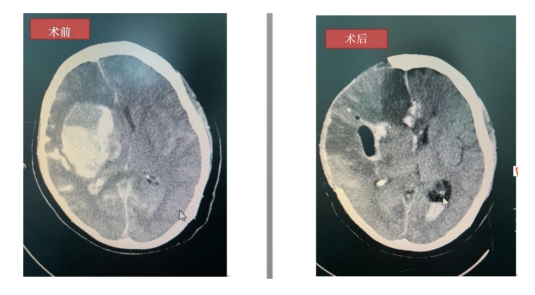

據(jù)了解,66歲的梁阿姨突然出現(xiàn)左側(cè)肢體無(wú)力伴頭暈3小時(shí),家人發(fā)現(xiàn)后立即送來(lái)我院治療,到院后梁阿姨出現(xiàn)意識(shí)、呼吸改變,瞳孔散大,急查頭部CT示右側(cè)基底節(jié)-放射冠區(qū)急性腦出血,量約118ML,并破入腦室系統(tǒng)及蛛網(wǎng)膜下腔。

術(shù)后復(fù)查頭顱CT提示梁阿姨顱內(nèi)大量的血腫基本已被清除干凈,目前生命體征平穩(wěn),后轉(zhuǎn)入我院重癥醫(yī)學(xué)科二區(qū)監(jiān)護(hù)治療。梁阿姨的成功救治,受益于我院綠色通道的暢通、手術(shù)團(tuán)隊(duì)精湛的技術(shù),以及“生命至上、患者至上”的服務(wù)理念。